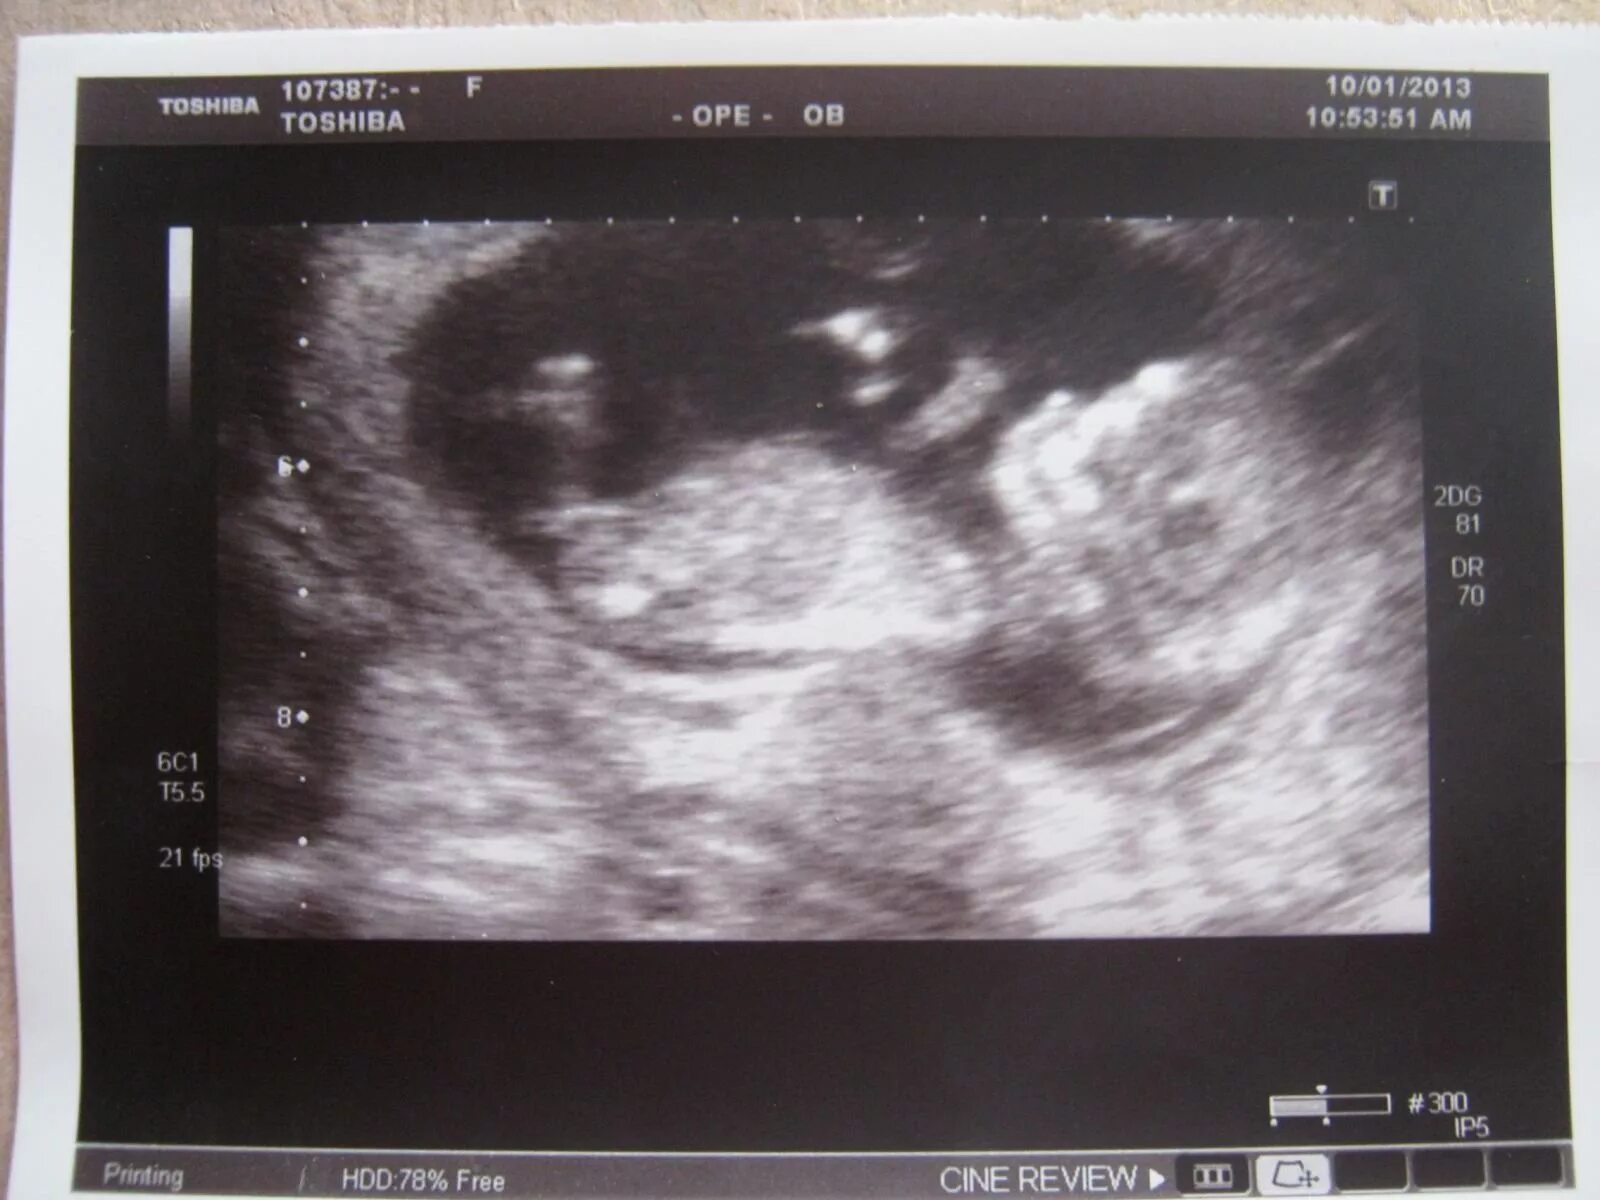

7 12 недель